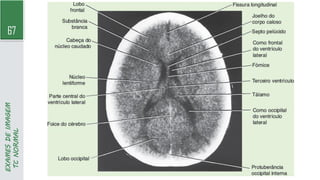

67

TC

NORMAL

74

RNM